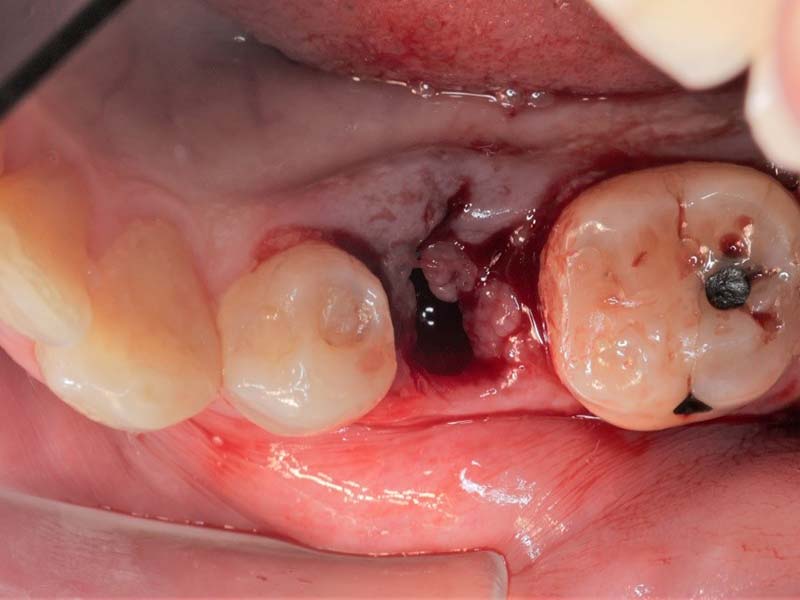

案例狀況:

牙齒蛀牙、斷裂。

拔牙前